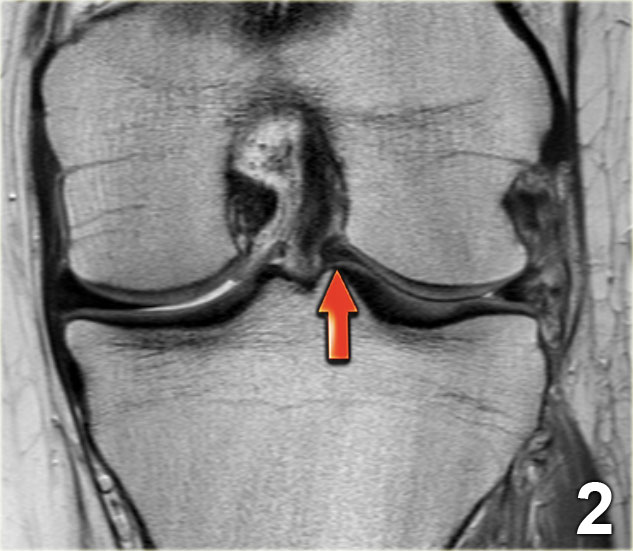

Như bạn đã đoán được qua tiêu đề của đoạn này, đây là một trường hợp sụn chêm lật (flipped meniscus).

Sụn chêm lật là một dạng đặc biệt của rách dạng quai xô (bucket-handle tear).

Sụn chêm lật xảy ra khi mảnh vỡ của sừng sau bị lật ra phía trước, khiến sừng trước của sụn chêm có vẻ to hơn bình thường.

Trên hình ảnh mặt phẳng coronal, trước tiên sẽ thấy sừng trước to và phồng lên.

Ở phía sau sẽ thấy sừng sau rất nhỏ.